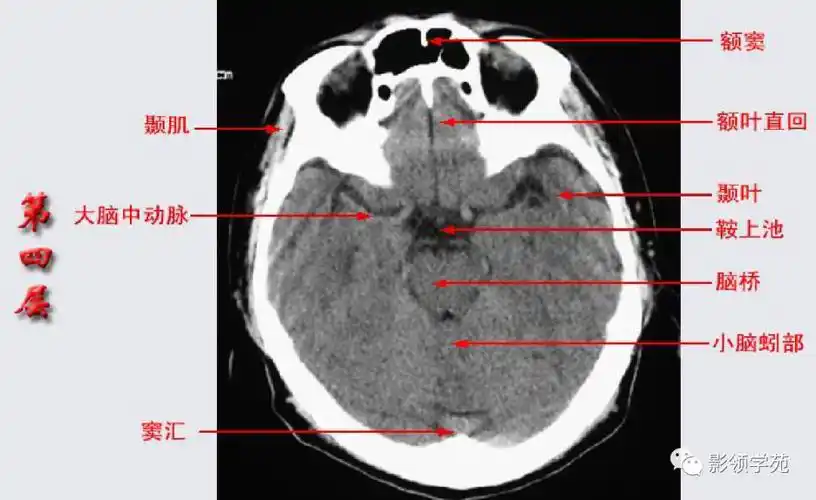

基底节区结构基底节(basal ganglia)(又称基底神经节)是指从胚胎端脑